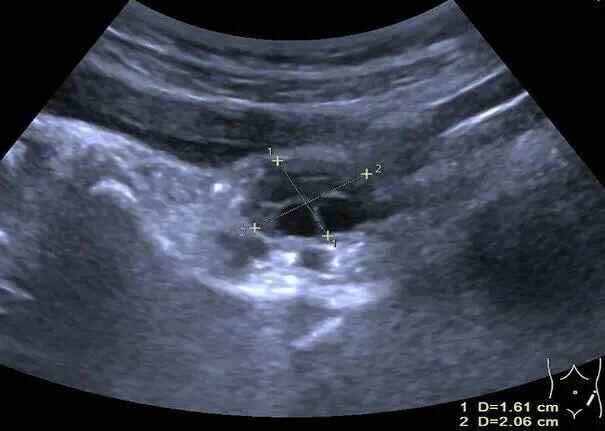

▲彩超下,婷婷的双侧卵巢内见8个直径大于4mm卵泡

▲左侧卵巢体积约4.9ml,内见4个直径大于4mm卵泡

▲右侧卵巢体积约3.2ml,内见4个直径大于4mm卵泡